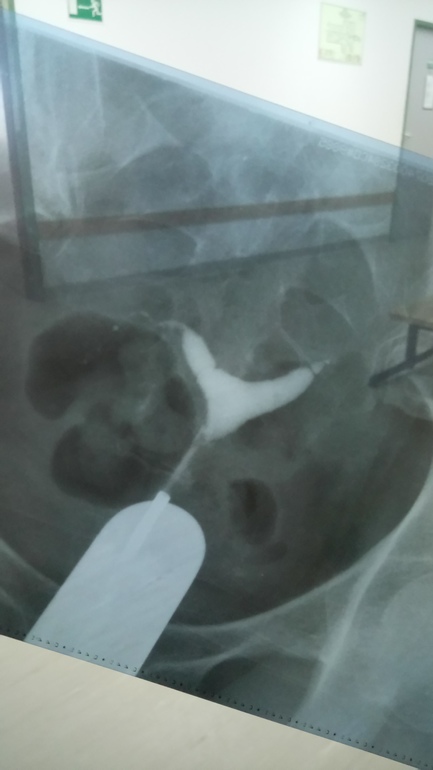

ГСГ, ЭХО, МСГ, ФертилоскопияСижу я в приёмной на госпитализацию и смотрю свой снимок гсг, а на нём.... Кто что видит? С левой стороны, как будто эмбрион))) Может это знак)